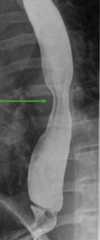

Normal barium swallow shows normal peristalsis (arrow)

Image by Hetal Verma.